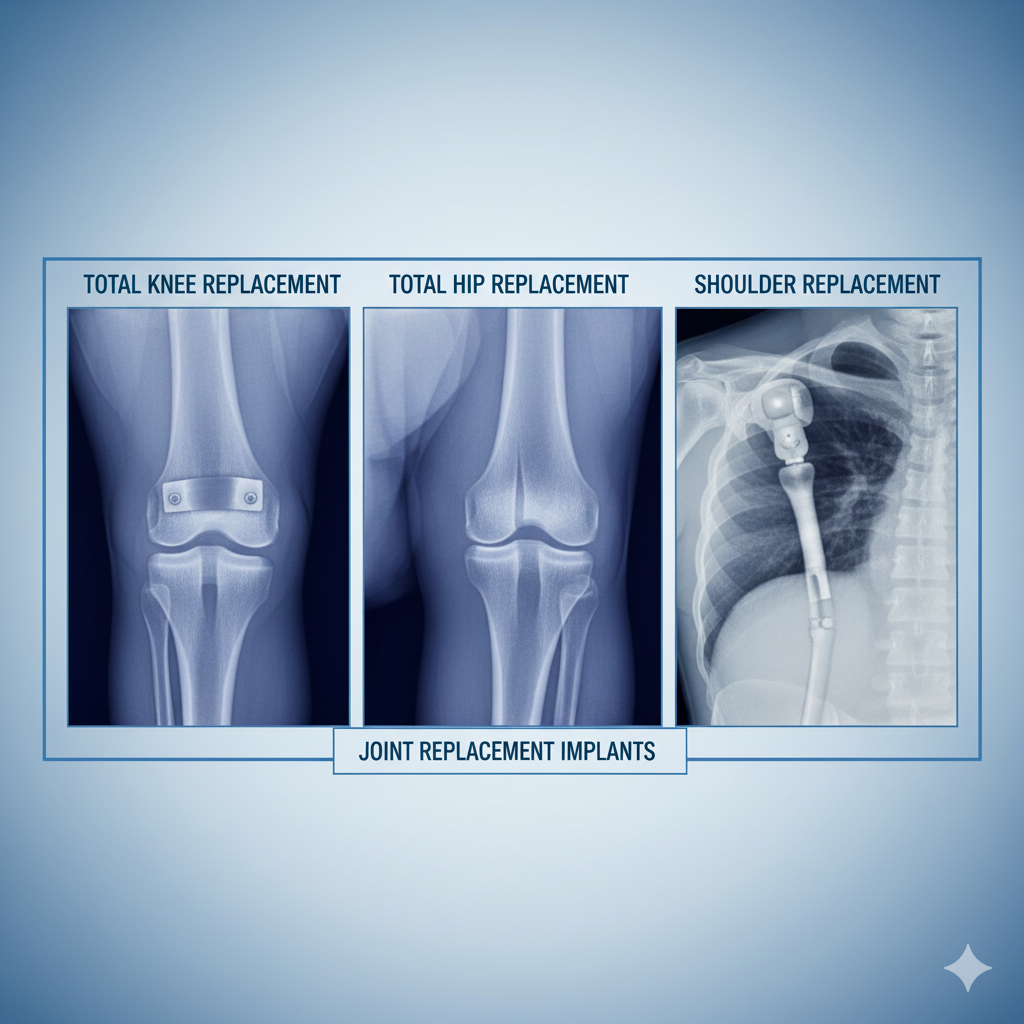

Best Orthopedics with Joint Replacement in kadkhoda Sonipat | Orthopedic Specialist

Orthopedics with Joint Replacement focuses on the diagnosis and treatment of bone, joint, and musculoskeletal disorders using advanced medical techniques. This blog explains knee, hip, and shoulder joint replacement procedures, their benefits, who needs j

Best Joint Replacement Hospital in Sonipat - Delhi Hospital

Best Joint Replacement Hospital in Sonipat - Delhi Hospital offers advanced knee, hip, and shoulde

Best Joint Replacement Hospital in Kharkhoda - Delhi Hospital

Looking for the best joint replacement hospital in Kharkhoda? Delhi Hospital is a trusted name, offering advanced joint replacement surgeries with expert orthopedic surgeons, modern technology, and personalized care. Whether it's knee, hip, or elbow r

Orthopedics with Joint Replacement: Regaining Mobility and Quality of Life

Delhi Hospital | Comprehensive Orthopedic Care in Delhi NCR

Joint pain and limited mobility can significantly affect one’s